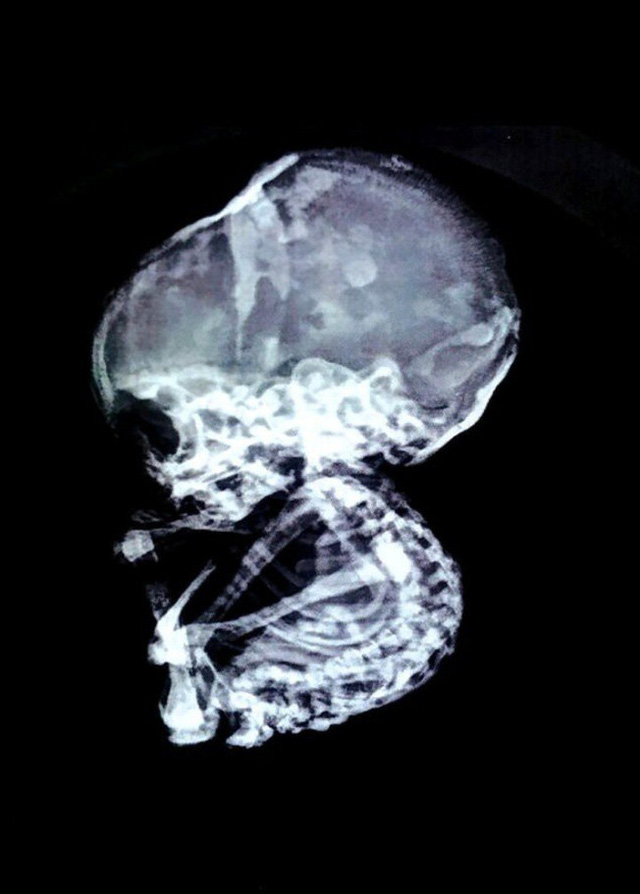

03/12/2017 16:3215 năm sau khi nạo thai, sốc vì bào thai vẫn còn nguyên trong bụng mẹ, hóa đá

3 năm trở lại đây, bà mẹ liên tục bị đau bụng và nôn mửa. Cô từng đến bệnh viện khám vài lần nhưng lần nào cũng chỉ được kê cho thuốc giảm đau và thuốc dạ dày.

Mãi gần đây bác sĩ mới phát hiện ra rằng có một bào thai lưu lại trong bụng cô. Ngay lập tức, bà mẹ được thực hiện cuộc phẫu thuật kéo dài 2 tiếng đồng hồ để loại bỏ hoàn toàn đứa trẻ đã hóa đá.

“Chụp chiếu cho thấy đường ruột cô ấy bị tắc nghẽn nghiêm trọng. Ống dẫn thức ăn bị một vật có cấu trúc giống như đá chèn ép. Thông thường bào thai chết lưu sẽ bị thối rữa, có thể gây nhiễm trùng cho cơ thể người mẹ nhưng trong trường hợp này, thai nhi đã tự ướp xác, tích tụ muối và hóa đá”, tiến sĩ Nilesh Junankar chia sẻ.

Vị bác sĩ phẫu thuật nội soi cũng cho biết các trường hợp bào thai hóa đá là vô cùng hiếm gặp, chỉ có khoảng 300 trường hợp được ghi chép trong lịch sử. Những trẻ sơ sinh hóa đá thường là kết quả của việc mang thai ngoài tử cung và không có cách nào rời khỏi cơ thể người mẹ.

Bất ngờ là dù có một thai nhi hóa đá trong bụng như vậy nhưng buồng trứng, tử cung, ống dẫn trứng của bà mẹ 52 tuổi vẫn hoàn toàn bình thường. Người phụ nữ tiết lộ mình đã mãn kinh sau 5 năm phá thai và lúc đó cũng không còn ở độ tuổi sinh con lý tưởng. Tuy nhiên vào thời điểm phá thai, cả bác sĩ sản khoa và bác sĩ phụ khoa đều khẳng định đứa trẻ đã được đưa ra ngoài thành công.